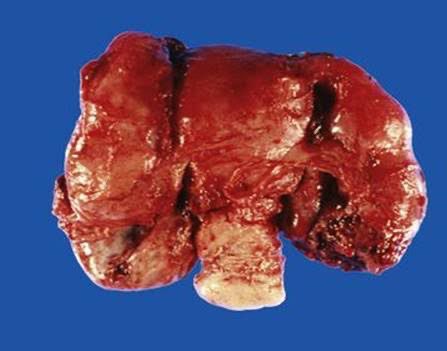

Pelvic inflammatory disease is a painful condition characterized by the infection of female genital tract. In most of the cases it occurs as a complication of Sexually transmitted diseases. The most commonly involved organisms in PID are Gonorrhoea and Chlamydia. Symptoms of PID are lower abdominal pain, dyspareunia, painful micturation, dysmenorrhea, vaginal discharge, etc. Complication of PID includes adhesions, tubo-ovarian abscess, salphingitis, endometritis. Picture demonstrates bilateral tubo-ovarian abscess due to PID. Picture credit: https://doctorlib.info/gynecology/hacker-moore-essentials-obstetrics-gynecology/22.html